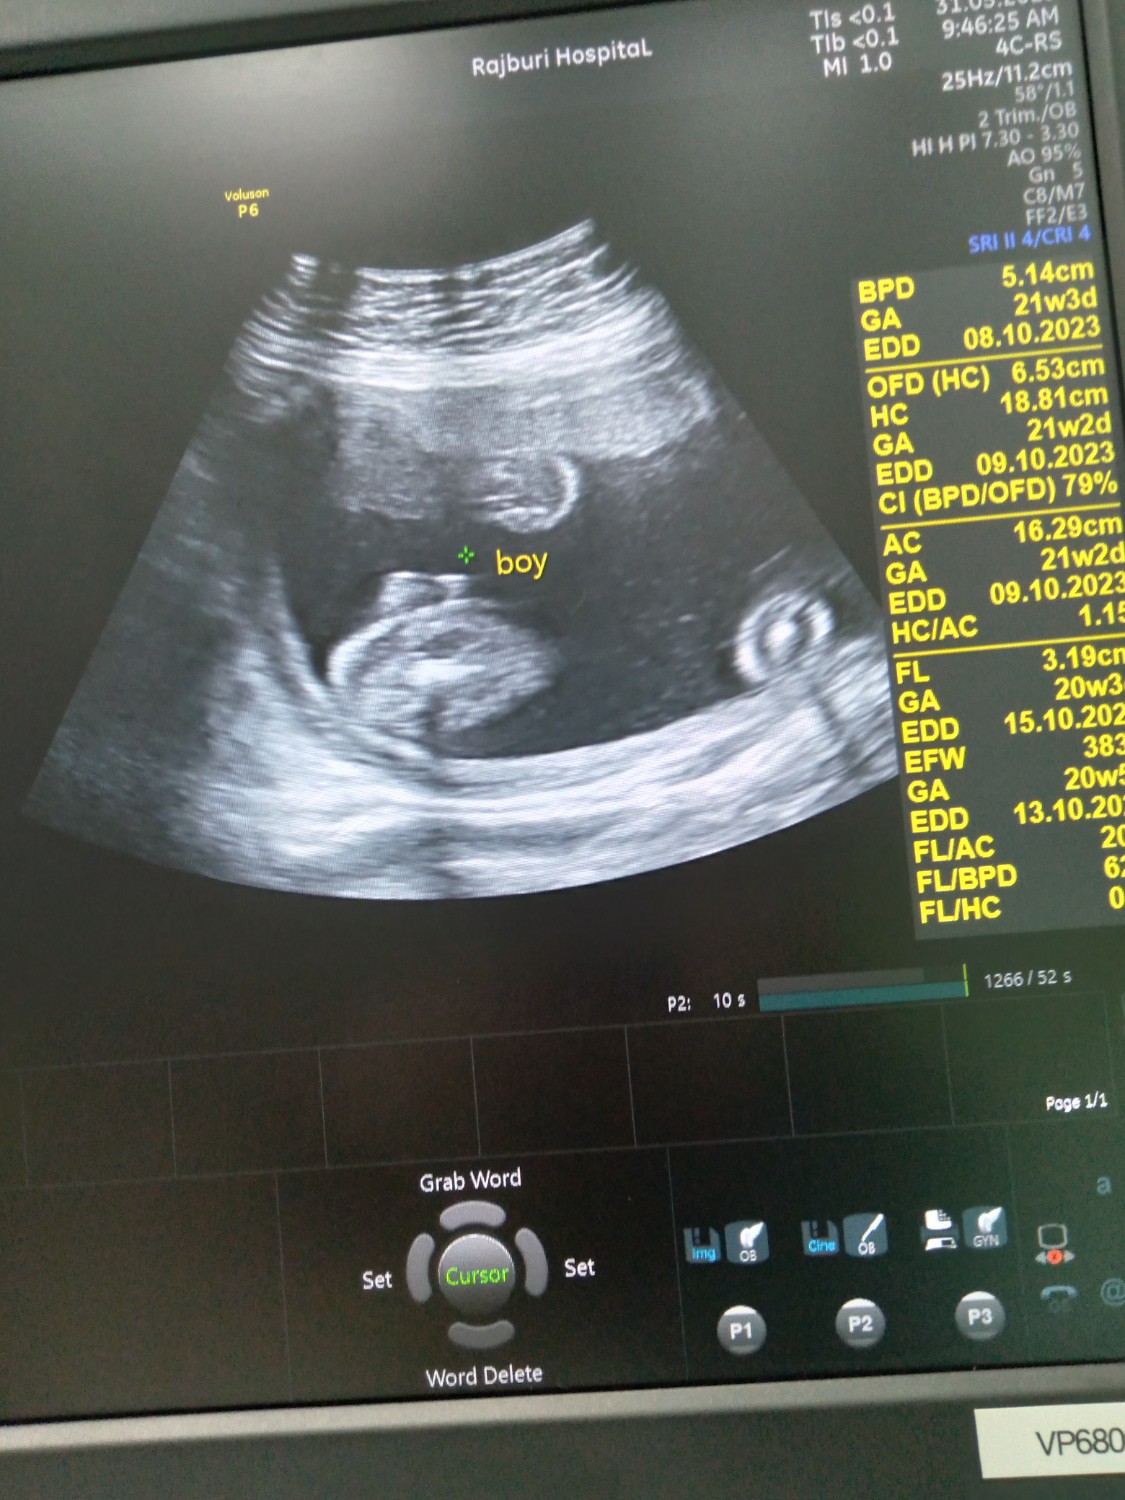

สอบถามหน่อยค่ะดูยังไงค้ะว่าได้เด็กผช